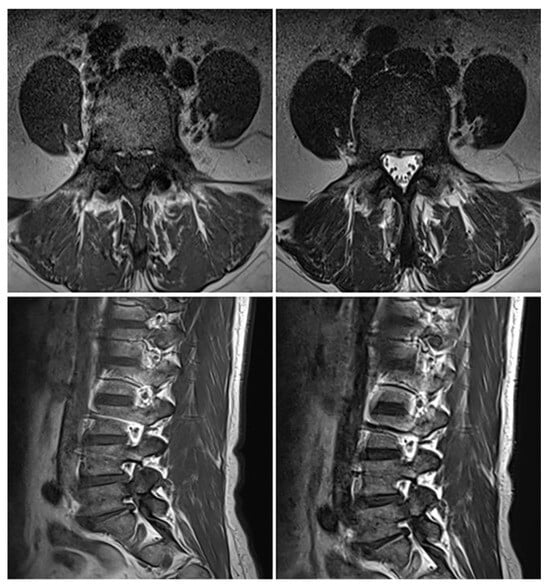

Although the patient’s symptoms had improved, imaging findings suggested that further bone healing was required. Therefore, the duration of brace application was extended by one additional month beyond the initially planned three months. At the four-month follow-up visit after the injury, a plain radiograph, dynamic flexion–extension lateral radiographs, and a CT scan were conducted. On plain radiographs, the bilateral L5 pedicle fractures appeared to show almost complete bony union, although the fracture lines could not be clearly assessed. Dynamic flexion–extension radiographs demonstrated no evidence of instability. To further determine whether additional bracing or activity restrictions were required, a CT scan was obtained for more detailed evaluation. The CT images allowed a more precise assessment and demonstrated cortical thickening with sclerotic change around the fracture margins, bone bridge formation, and fracture gap narrowing, indicating interval reduction in the fracture lines and near-complete union. Pedicle stress reaction was also assessed on follow-up imaging. Stress-related changes such as diffuse pedicle sclerosis, excessive cortical hypertrophy, absence of fracture gap narrowing, and the presence of new fissures or lucencies were specifically checked. None of these findings were observed, indicating no evidence of persistent pedicle stress. (Figure 4). The patient was permitted to remove the brace and resume normal activities without motion restrictions. The patient expressed satisfaction that surgical treatment was not required, although wearing the brace for a long period was uncomfortable. However, she stated that the brace greatly helped relieve her pain. The total follow-up duration was four months from the onset of injury. The patient’s symptoms progressed from an NRS score of 5 to 7 on admission, but improved to an NRS score of 3 with conservative management, including medication, TLSO application, and activity restriction during hospitalization. By the four-month follow-up, her pain had completely resolved, and imaging studies demonstrated near-complete bony reunion of the bilateral pedicle fractures.

Figure 4. Four-month follow-up plain radiograph and CT scan after the injury. (A) The plain radiograph suggests almost complete bony union of the bilateral L5 pedicle fractures, although clear assessment of the fracture lines is limited. (B) The CT scan shows sclerotic change around the fracture margins and an interval reduction in the fracture lines.